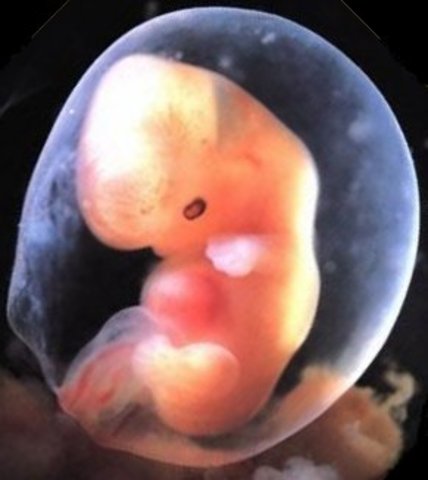

• Week 5: The Embryonic Stage Begins

Week 5: The Embryonic Stage Begins

In this stage, the placenta is beginning to form. The embryo will double in size from the week 4 embryo by the edn of week 5.

• Week 6: The Heart Begins to Beat

Week 6: The Heart Begins to Beat

Spinal cord is closing, brain is splitting into five parts, a tiny little heart forms and will begin to beat, and the arms and legs are begiining to go into place from their cells. Oxygen and nourishment will be given to the baby through its developing umbilical cord.